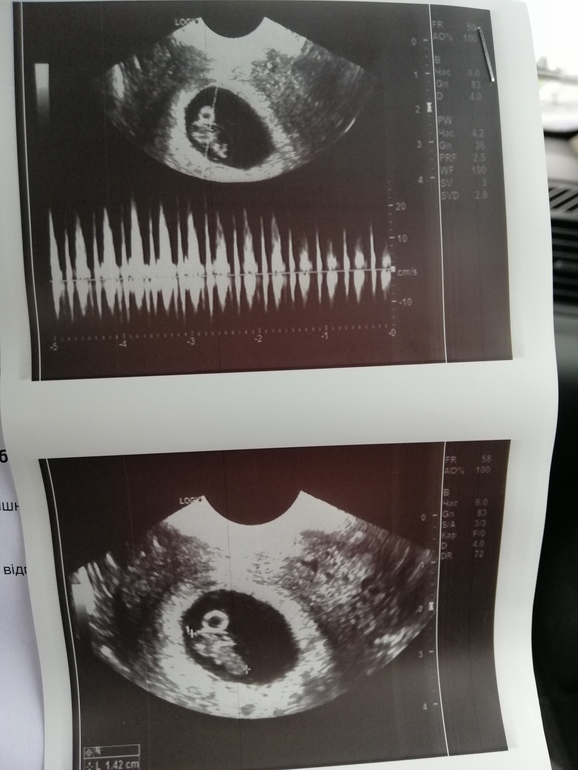

Сходила на узи, один малыш, каже мы его уже любим🥰, все по нормам, теперь в поисках врача, и где стать на учёт.